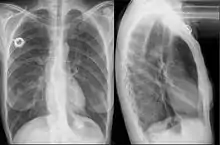

Esophageal stent

An esophageal stent is a stent (tube) placed in the esophagus to keep a blocked area open so the patient can swallow soft food and liquids. Esophageal stents may be self-expandable metallic stents, or made of plastic, or silicone, and may be used in the treatment of esophageal cancer.

As of 2009, covered self-expanding metal stents were the only FDA-approved to be placed permanently. Occasionally, these stents may be placed as part of a clinical trial or as off-label use to repair esophageal leaks or fistulae. They are placed using the guidance of fluoroscopy (x-ray) and endoscopy. Usually, they are left in for less than four weeks.[2]